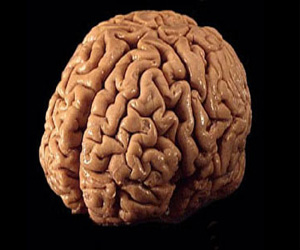

دراسات عن التحورات الجينية تلقى ضوءًا جديدًا على الفصام

أظهرت دراسة أن الأشخاص المصابين بالفصام يعانون من تحورات جينية تتجمع فى بروتينات ذات دور محورى فى وظائف المخ، مما يطرح نظرة جديدة للمرض ويربط بينه وبين اضطرابات دماغية أخرى مثل التوحد. وجاء فى ورقتين بحثيتين نشرتا فى دورية نيتشر، وتشكلان معا أكبر دراسة جينية من نوعها أن بعض العلماء قاموا بتحليل تحورات جينية جديدة فى الأشخاص المصابين بالفصام، ووجدوا أنها تخل بعمل مجموعة من البروتينات تقوم بوظائف ذات صلة بالمخ. وتوجد التحورات الجينية الجديدة فى الأشخاص المصابين، ولكنها لا توجد فى آبائهم مما يعنى أنها ليست وراثية. وقال الباحثون إنه فضلا عن تحديد كيفية تأثير التحورات الجينية على وظيفة المخ تشير نتائج الدراسة أيضا إلى وجود تداخل مع أسباب اضطرابات دماغية أخرى، مثل التوحد والإعاقة الذهنية. وقال ميك أودونوفان من جامعة كارديف البريطانية الذى شارك فى إعداد البحث "حقيقة أننا استطعنا تحديد درجة من التداخل بين الأسباب الرئيسية للفصام وأسباب التوحد والإعاقة الذهنية تشير إلى أن هذه الاضطرابات قد تشترك فى بعض الآليات. وأضاف أن النتائج "تظهر لنا أننا استطعنا للمرة الأولى فهم واحدة من عمليات المخ الرئيسية التى تصاب بخلل فى هذا الاضطراب." ويعد الفصام واحدا من أكثر الأمراض النفسية الخطيرة شيوعا إذ يصيب نحو واحد بالمئة من سكان العالم.. ولم تتضح للعلماء أسبابه بالضبط ولكنهم يعتقدون أنها قد تكون مزيجا من الاستعداد الجينى لهذا الاضطراب وبعض العوامل البيئية. وقام الباحثون بفحص عينات من الحمض النووى "دى.إن.إيه" من 623 مريضا بالفصام وآبائهم، وفى دراسة منفصلة قام فريق آخر بتحليل التركيبات الجينية لأكثر من 2500 مصاب بالفصام ولنفس العدد تقريبا من غير المصابين للمقارنة بينهم. ووجد الباحثون أن التحورات الجديدة تلعب دورا فى الإصابة بالفصام، ويبدو أنها تتجمع فى بروتينات تساهم فى تنظيم قوة الاتصال بين الخلايا العصبية وتلعب أدوارا مهمة فى نمو المخ والتعلم والذاكرة والمعرفة.